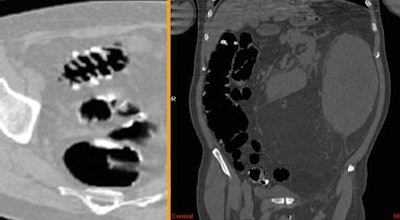

![]() |

| Above and below: Despite suboptimal distension, VC detected two significant polypoid lesions in the sigmoid colon of a 61-year-old paraplegic with fecal occult blood, following unsuccessful colonoscopy. The patient's parents had both died of colon cancer. Digital subtraction was used to detect the fluid-submerged polyps. |